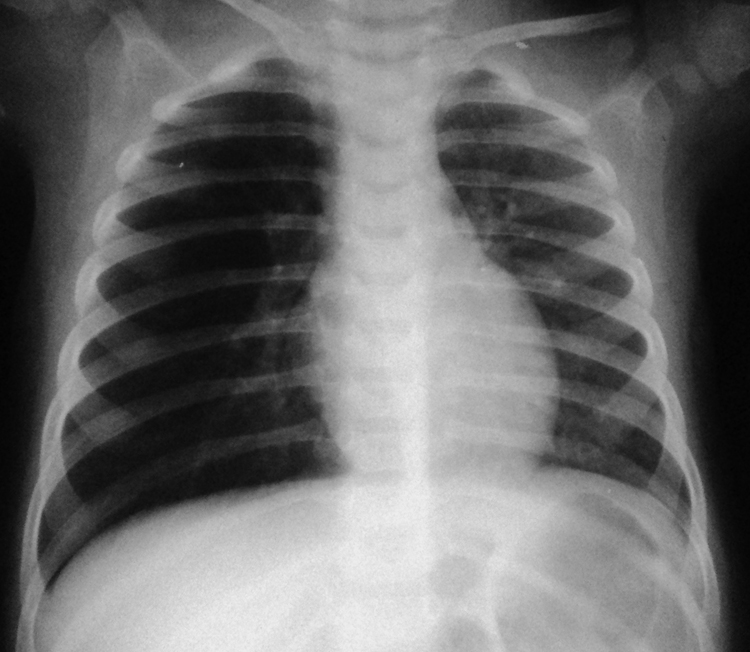

What tests are usually done to diagnose the problem?

Along with a physical examination and medical history, imaging studies are usually done to evaluate whether a baby has TE fistula and/or esophageal atresia. X-rays are taken to look at the chest and abdomen.

A small tube may also be placed into the mouth or nose and then guided into the esophagus. With esophageal atresia, the tube usually cannot be inserted very far into the esophagus. The tube’s position in the esophagus can also be seen with the X-ray.

If your baby has problems eating or breathing, chokes during feeding, or coughs up a lot of fluid or mucus, he or she may have TEF or EA. = TOF or OA Your health care provider will take an X-ray to learn more. This will show if the baby has one or both problems. The X-ray is often done with a feeding tube put into the baby’s esophagus to see if the tube reaches the stomach.

Chest-X-Ray of Foreign Body in Lungs